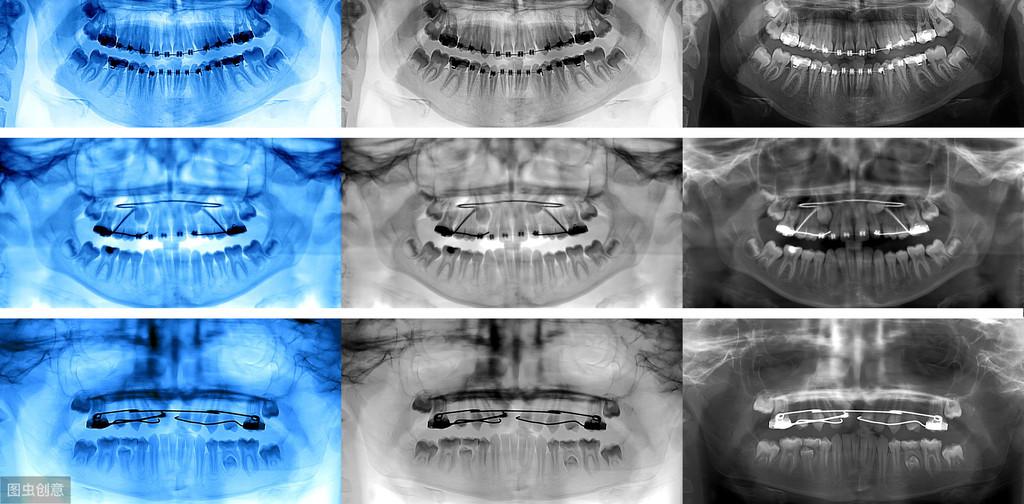

牙齒種植術(shù)是目前好的缺失牙齒修復(fù)技術(shù)之一,因?yàn)樗姆N植技術(shù)是通過手術(shù)將種植體植入到牙槽骨里,獲得了骨組織的固位支持,所以種植牙齒的穩(wěn)定性、性和使用年限都高,因此,種植牙從發(fā)展到現(xiàn)在也獲得了醫(yī)學(xué)界專家廣泛的認(rèn)可和大量有需要患者的喜愛。

也正是因?yàn)樾枰ㄟ^手術(shù)的方法將種植體植入到牙槽骨里,所以也會(huì)有部分患者會(huì)心存顧慮,針對這些備受關(guān)注的問題,我們今天就來好好的聊一下;

一、種植牙的性怎樣?牙齒種植是一種系數(shù)很高的修復(fù)方法,他的創(chuàng)傷很小,在不損傷附近牙齒的情況下只針對缺失的牙齒做修復(fù);且牙齒種植術(shù)發(fā)展了40多年,經(jīng)過不斷的科技進(jìn)步和技術(shù)更新,現(xiàn)在的牙齒種植術(shù)已經(jīng)成熟了,所以無需過度擔(dān)心問題。